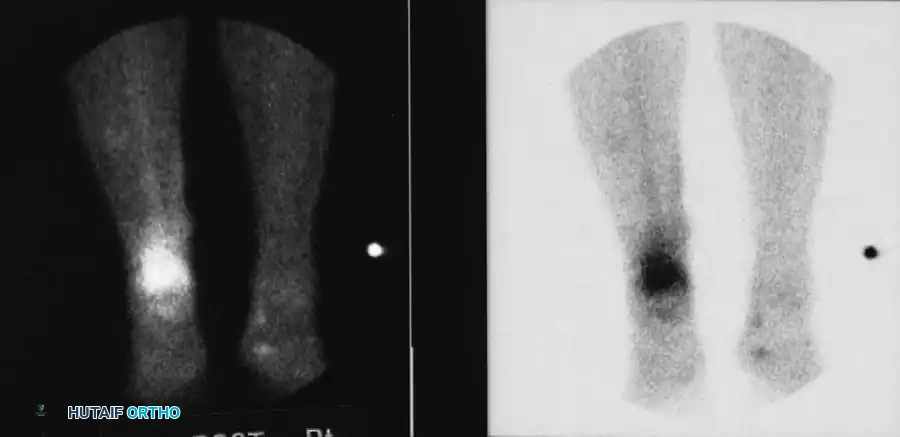

Radionuclide Scintigraphy

While radiographs and CT provide structural data, radionuclide scanning provides a physiological map of osteoblastic activity and regional blood flow. It is particularly useful in patients with metallic implants where MRI is contraindicated or obscured by artifact.

Technetium-99m Phosphate:

The most commonly used isotope, capable of detecting osteomyelitis within 48 hours of clinical onset. The standard technique is the Three-Phase Bone Scan:

1. Flow Phase (Radionuclide Angiogram): Demonstrates regional perfusion.

2. Equilibrium/Blood Pool Phase: Shows relative vascular flow and extracellular distribution (tissue hyperemia).

3. Delayed Phase (2-4 hours post-injection): Reflects osteoblastic activity.

Image

Fig. 15-4 Three-phase bone scan showing intense, focal uptake characteristic of osteomyelitis.

Table 15-3: Three-Phase Bone Scan Uptake Patterns

Pathology Flow Phase Equilibrium Phase Delayed Phase

Osteomyelitis Increased (↑) Increased (↑) Increased (↑)

Cellulitis Increased (↑) Increased (↑) Normal/Decreased (↔/↓)

Osteoarthritis Normal (↔) Normal (↔) Increased (↑)

Pitfall: A "cold" scan can occur in acute osteomyelitis if regional blood flow is completely occluded by subperiosteal pus, severe vasospasm, or massive soft-tissue swelling. Furthermore, Tc-99m scans are unreliable in neonates (< 6 weeks old), yielding false negatives in up to 60% of cases.